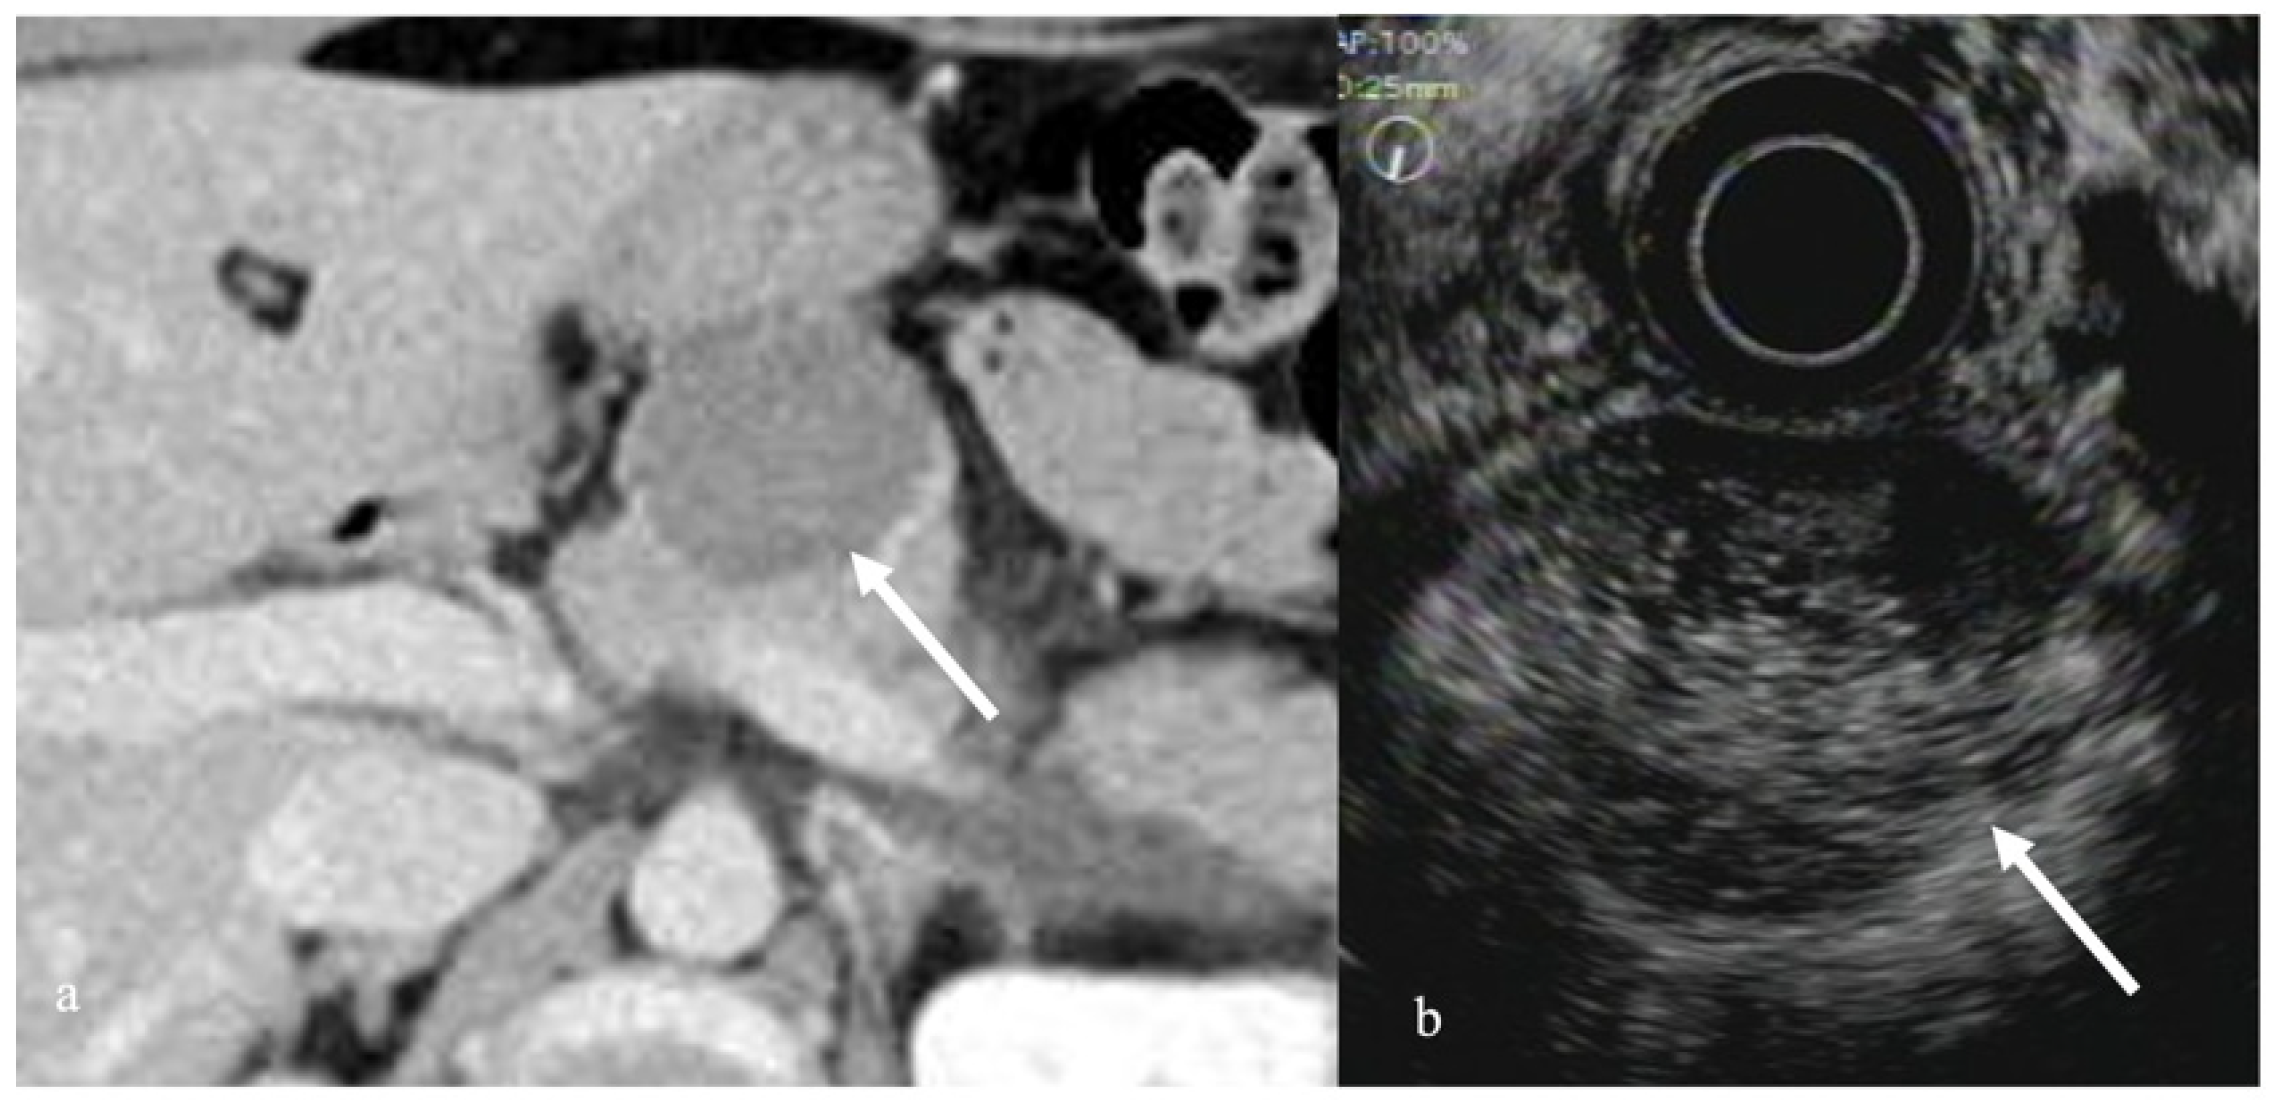

3.3. Pancreatic Cystic Tumors

- Harima, H.; Kaino, S.; Shinoda, S.; Kawano, M.; Suenaga, S.; Sakaida, I. Differential diagnosis of benign and malignant branch duct intraductal papillary mucinous neoplasm using contrast-enhanced endoscopic ultrasonography. World J. Gastroenterol. 2015, 21, 6252–6260. [Google Scholar] [CrossRef]

- Ohno, E.; Hirooka, Y.; Itoh, A.; Ishigami, M.; Katano, Y.; Ohmiya, N.; Niwa, Y.; Goto, H. Intraductal papillary mucinous neoplasms of the pancreas: Differentiation of malignant and benign tumors by endoscopic ultrasound findings of mural nodules. Ann. Surg. 2009, 249, 628–634. [Google Scholar] [CrossRef]

- Yamashita, Y.; Ueda, K.; Itonaga, M.; Yoshida, T.; Maeda, H.; Maekita, T.; Iguchi, M.; Tamai, H.; Ichinose, M.; Kato, J. Usefulness of contrast-enhanced endoscopic sonography for discriminating mural nodules from mucous clots in intraductal papillary mucinous neoplasms: A single-center prospective study. J. Ultrasound Med. 2013, 32, 61–68. [Google Scholar] [CrossRef]

- Yamamoto, N.; Kato, H.; Tomoda, T.; Matsumoto, K.; Sakakihara, I.; Noma, Y.; Horiguchi, S.; Harada, R.; Tsutsumi, K.; Hori, K.; et al. Contrast-enhanced harmonic endoscopic ultrasonography with time-intensity curve analysis for intraductal papillary mucinous neoplasms of the pancreas. Endoscopy 2016, 48, 26–34. [Google Scholar] [CrossRef]

- Zhong, L.; Chai, N.; Linghu, E.; Li, H.; Yang, J.; Tang, P. A prospective study on contrast-enhanced endoscopic ultrasound for differential diagnosis of pancreatic cystic neoplasms. Dig. Dis. Sci. 2019, 64, 3616–3622. [Google Scholar] [CrossRef]